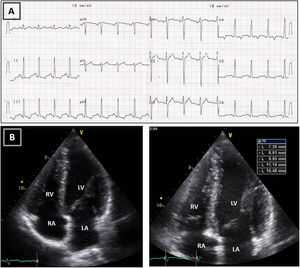

Follow-up assessment was performed four months later. He had reportedly respected our warning and barely exercised in the meantime. While still abnormal, the ST-segment depression and deeply inverted T waves had become less prominent (Figure 3). We repeated the TTE and had a similar impression: although maximum wall thickness in the apex was significantly decreased (10-11 mm) and not diagnostic of HCM, the TTE seemed clearly abnormal, given the small cavity, the abnormal geometry and the apical gradient (Figures 3 and 4 and Video 2).

Transthoracic echocardiogram after detraining. Note the abnormal shape of the left ventricular cavity (small cavity size, prominent papillary muscle, with apical cavity obliteration in systole (A) and increased flow velocity (arrow) (B) suggestive of a myopathic left ventricle, rather than adaptive remodeling following training. LA: left atrium; LV: left ventricle; RA: right atrium; RV: right ventricle.